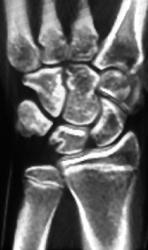

Tuberculosis (TB) Osteomyelitis